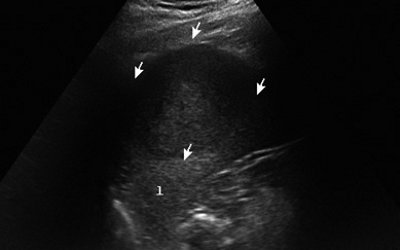

При УЗИ больного Т. селезенка увеличена (площадь - 68 см²), контуры ее неровные, четкие, структура паренхимы неоднородная за счет наличия в средней трети образования, деформирующего латеральный контур селезенки, однако не доходящего до ее ворот. Образование округлой формы, по структуре солидное, гипоэхогенное, с четкими ровными контурами, размером 65x60x53 мм (рис. 1).

Рис. 1. Эхограмма гамартомы селезенки (В-режим), гамартома указана стрелками.